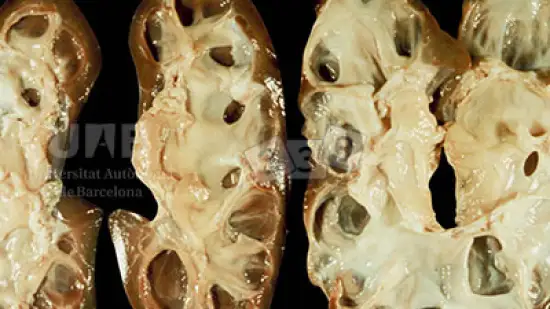

Qual é a possível causa desta lesão encontrada na necropsia de um animal que apresentou febre e letargia?